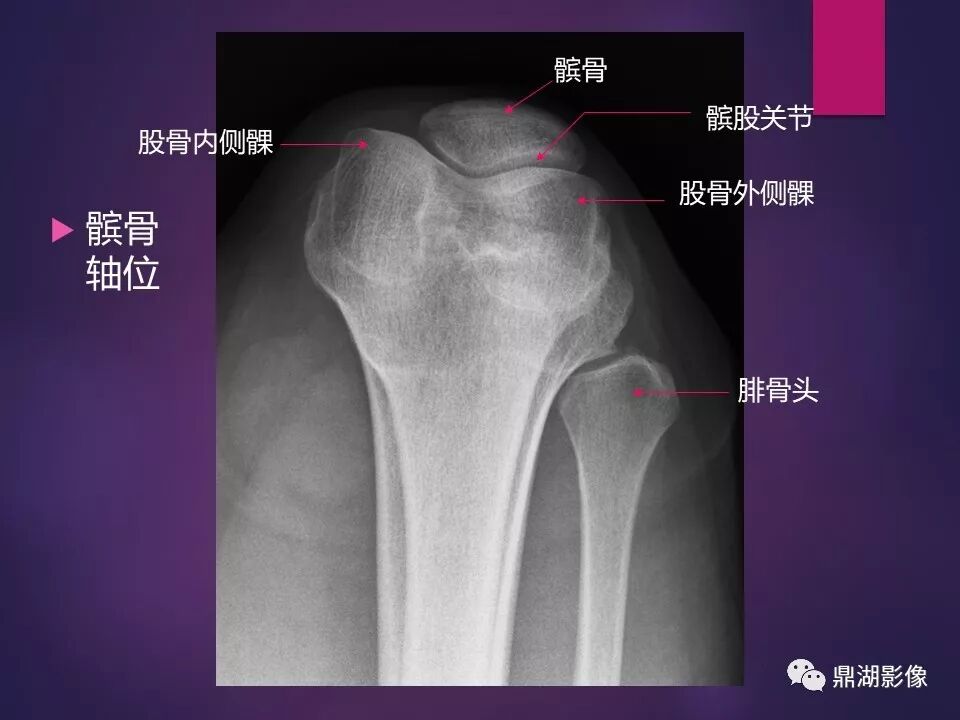

来源于:鼎湖影像 贵阳医学院医学影像系